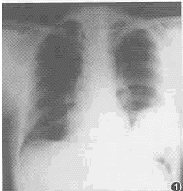

临床放射学杂志000627 患者 男,48岁。发现左胸壁突出2个月。胸 片后前位示左下肺野约8cm×11cm软组织肿块。左侧位片椭圆形肿块与斜行肋骨相一致。稍 右前斜位点片见肿块部分向侧胸壁突出,边界清楚,无钙化。左第7前肋骨约9cm溶骨性破坏 ,无明显骨膜反应(图1~3)。

图1 左下肺野巨大软组织肿块,边界清楚,无钙化